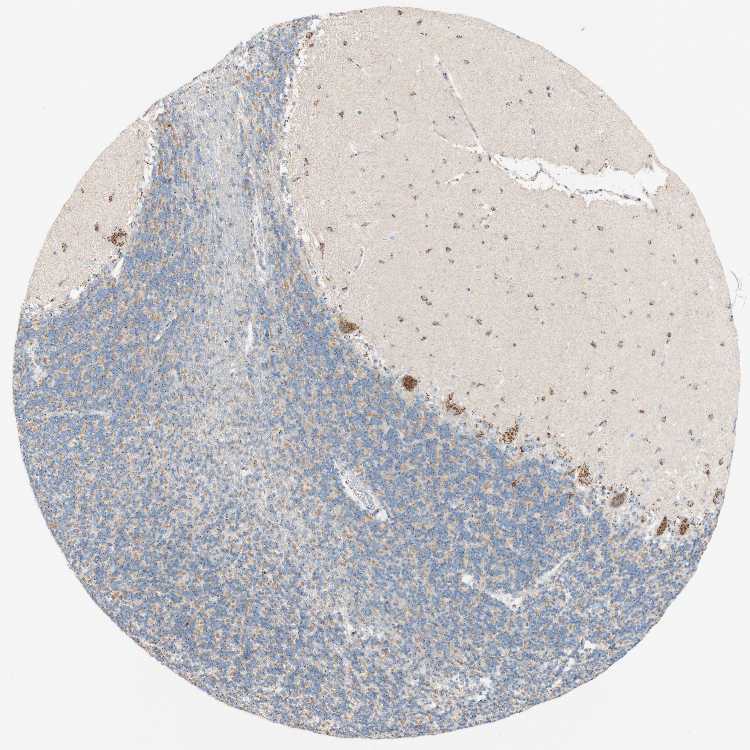

TISSUE PRIMARY DATA CEREBELLUM Show tissue menu

CEREBELLUM - Antibody stainingi

Antibody staining in the annotated cell types in the current human tissue is reported as not detected, low, medium, or high, based on conventional immunohistochemistry profiling in selected tissues. This score is based on the combination of the staining intensity and fraction of stained cells.

Each image is clickable and will lead to virtual microscopy that enables deeper exploration of all samples and also displays staining intensity scores, fraction scores and subcellular localization as well as patient and tissue information for each sample.

Antibody HPA011008Antibody HPA011555

Purkinje cells HighHigh

Cells in granular layer MediumHigh

Cells in molecular layer HighHigh